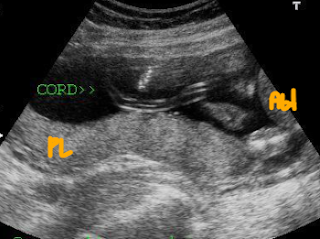

Sample Location: Preferably in a free-floating loop of the cord (mid-portion, not near the fetus or placenta).

| Free loop of umbilical cord (not near fetal abdomen or placenta) |